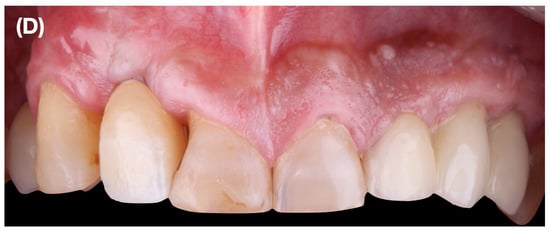

Prior to surgery, the temporary implant-supported crown was removed to facilitate access to the surgical site and the patient rinsed his mouth for 1 min with a chlorhexidine mouthwash. The surgical technique began with the preparation of the recipient area; for this purpose, a partial-thickness sulcular incision was made at the level of the PSTD, followed by dissection apically and laterally towards teeth 1.3 and 1.1, extending 3 to 5 mm from the PSTD to allow entry of the CTG and its stabilization. Subsequently, an apical horizontal incision was made on the vestibular aspect of the bottom of the vestibule, leaving a bridge of tissue that would serve as a double blood supply to the graft (Figure 3A). The tissue coronal to the incision was later repositioned apico-coronally maintaining the marginal integrity of the tissue.

Figure 3.

(A): Apical horizontal incision at the bottom of the vestibule. No vertical releasing incisions are made. (B): Sub-epithelial connective tissue graft. (C): Double-crossed sutures are used for the fixation of the buccal soft tissue complex, including the connective tissue graft. The horizontal incision in the vestibule is not sutured. (D): Intraoral view immediately after removing the suture. (E): Clinical situation 4 months after surgery. (F): Postsurgical wound healing at 10 months.

Once the recipient bed was created, a CTG was obtained from the palatal masticatory mucosa; that graft was sutured using two horizontal mattress stitches, one located mesially and the other distally to the envelope (Figure 3B). For further adaptation, stabilization, and traction of the CTG and papillae coronally, a double-crossed vertical suspensory stitch was performed using 5–0 non-absorbable suture (5–0 Polyamide, Serag-Wiessner GmbH & Co. KG, Zum Kugelfang, Naila, Germany). The base where the horizontal incision was made was left to heal by secondary intention (Figure 3C).

A control was performed one week after the intervention and, after 15 days, we removed the suture and observed the revascularization of the graft and epithelialization of the horizontal incision made at the bottom of the vestibule (Figure 3D). Follow-up photographs were taken 4 months and 10 months after the procedure (Figure 3E,F).